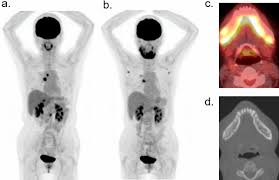

An FDG PET CT scan uses a glucose-based radioactive tracer called FDG. Since cancer cells, infections, and inflammatory tissues consume more glucose than normal cells, this scan highlights abnormal metabolic activity in the body. The Best FDG PET CT Scan in HauzKhas helps doctors detect diseases that may not be visible on routine CT or MRI scans.

Cancer detection and staging

Monitoring response to chemotherapy or radiation

Detecting cancer recurrence

Evaluating unexplained fever or weight loss

Identifying infections and inflammatory conditions